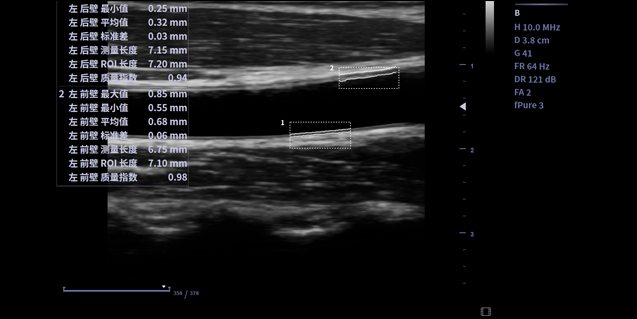

临床图像

高密线阵探头L13-3

256阵元数,61.5*23.4成像范围,更适用于乳腺扫查。